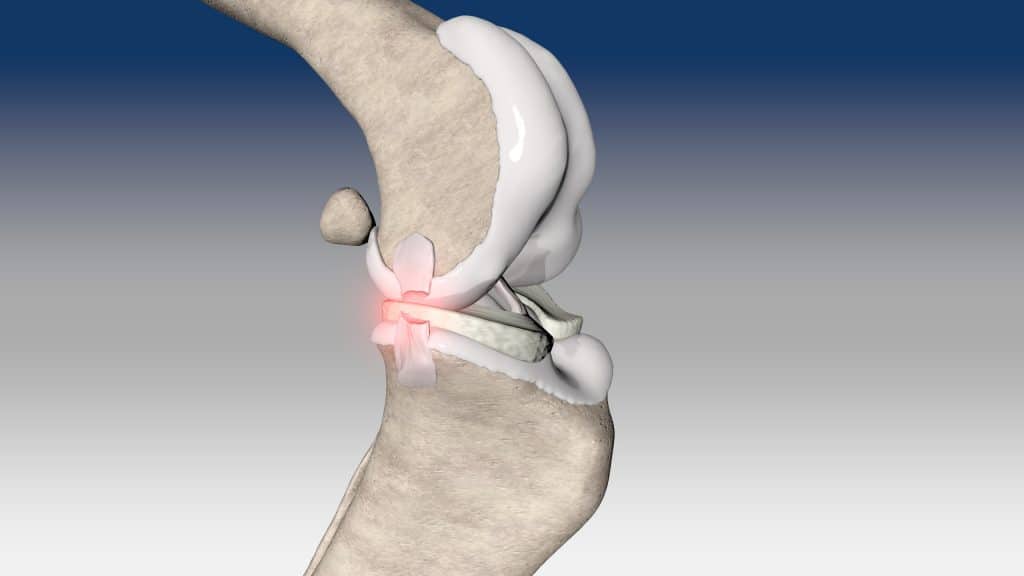

Ruptura kraniálního zkříženého vazu je hlavní příčinou ortopedických konzultací u psů. Tento stav se obvykle léčí chirurgicky pomocí osteotomických technik, mimokloubní stabilizace nebo intraartikulární rekonstrukce.

V případě ruptury kraniálního zkříženého vazu umožňuje ExtraTape® extraartikulární rekonstrukci co nejblíže izometrii původního vazu, čímž rychle a trvale stabilizuje koleno bez uzlů a zvlnění, což je slabina tradičnějších technik extraartikulární stabilizace. Ty jsou zde nahrazeny pevným ukotvením kosti pomocí interferenčního šroubu.

Řešení, které respektuje původní anatomii, obnovuje funkci postiženého vazu a je dostupné v rámci otevřené nebo artroskopické chirurgie.